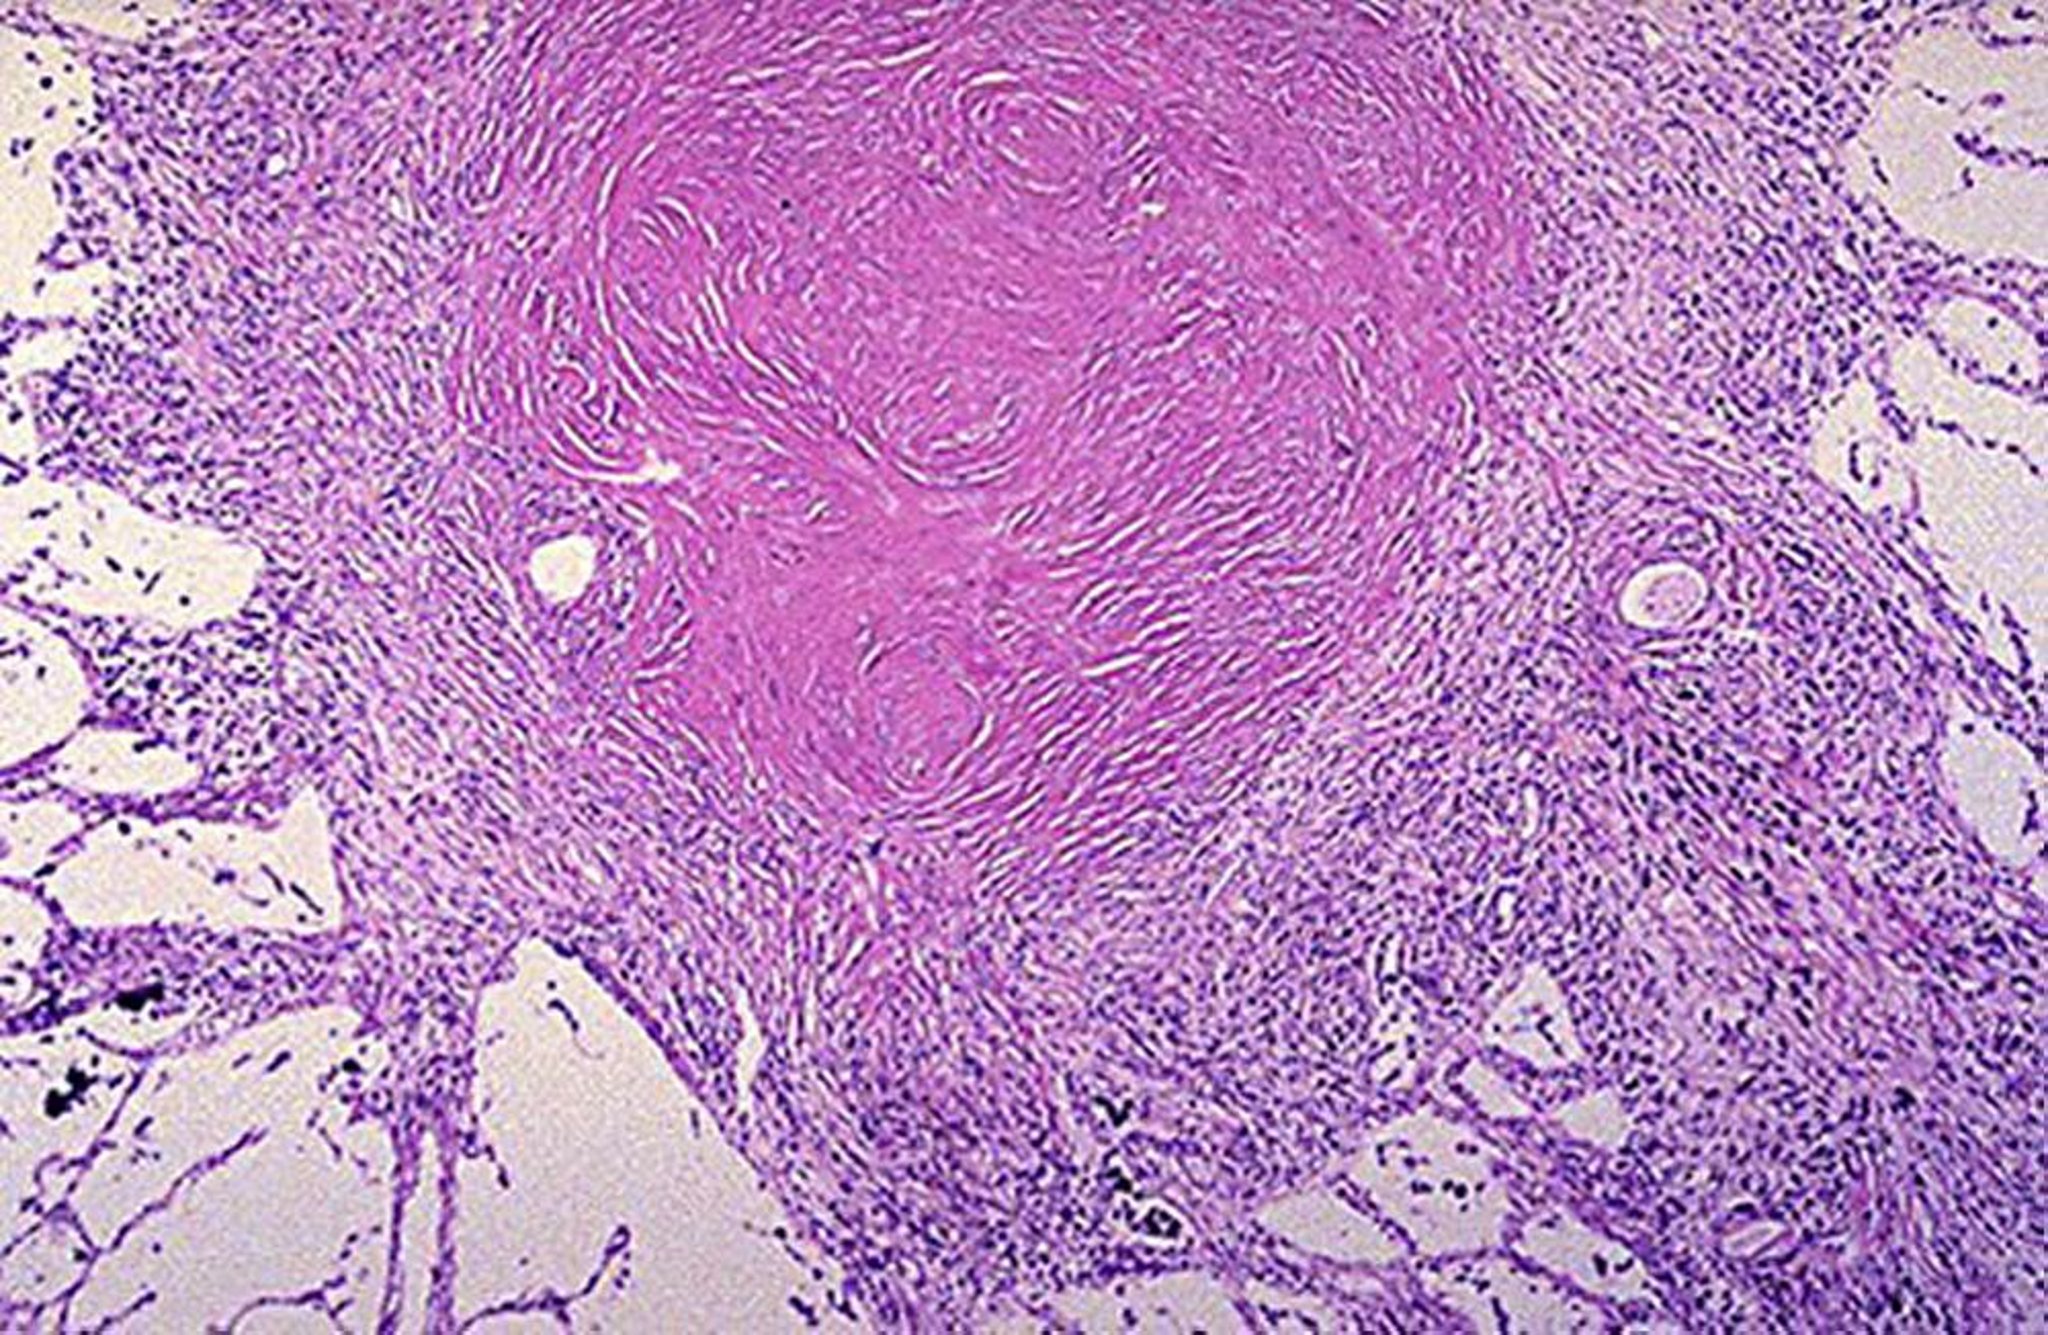

Nódulo silicótico

Image courtesy of David W. Cugell, MD.